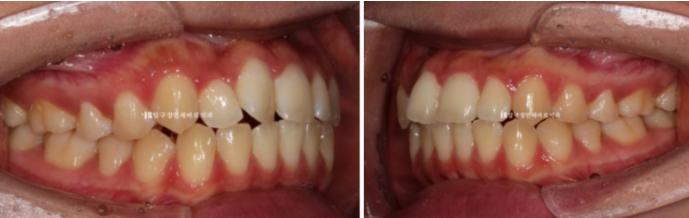

어금니 교합은 나쁘지 않은 편이라서 단기 앞니 부분교정 권유드렸습니다

23.12

앞니 부분교정은 배열 이외의 별다른 기능이 없는 대신 작고 심플한 MTA 미니튜브나 설측 2D교정장치를 사용합니다.

하지만 이 환자분은 덧니 이외에도 앞니 물리는 것이 얕은 절단교합을 보였기에 앞니 배열 후 고무줄을 걸어 절단 교합도 어느정도 해결하기로 했습니다.

따라서 고무줄 거는 기능이 있는 장치를 클리피씨 부착하고 교정 시작했습니다.